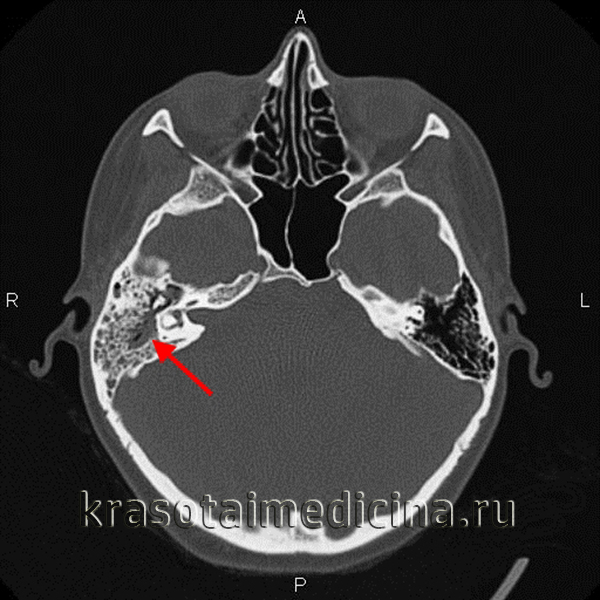

Диагноз устанавливают на основании клинической картины; большое значение имеет рентгенологическое исследование. Рентгенографию проводят в боковой и косой проекциях. Рентгенологическая картина начальной экссудативной стадии характеризуется только затемнением сосцевидных ячеек; симптомы нарушения костной структуры отсутствуют. При деструктивных явлениях в костной ткани наблюдается снижение интенсивности теней костных перекладин, местами почти полное их отсутствие. Гнойное расплавление рентгенологически проявляется очагом разрежения костной ткани (рис.), которое при образовании абсцесса становится более интенсивным, полностью теряет свою структуру.

- Рентгенография височной кости. В экссудативной стадии мастоидита обнаруживает завуалированные в результате воспаления ячейки и нечетко различимые перегородки между ними. Рентгенологическая картина пролиферативно-альтеративной стадии мастоидита характеризуется отсутствием ячеистой структуры сосцевидного отростка, вместо которой определяется одна или несколько больших полостей. Лучшая визуализация достигается при проведении КТ черепа в области височной кости.